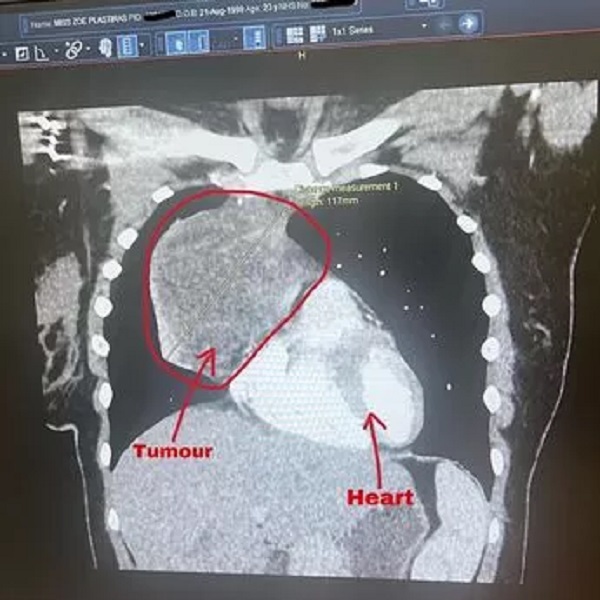

6 din 6 | Tumora de 12 cm a lui Zoe Plastiras

Zoe Plastiras era însărcinată în 32 de săptămâni, când medicii au descoperit o tumoare de 12 cm, de mărimea unui grapefruit, care creștea lângă inima ei.

Tumora era uriașă, de peste 12 cm în lungime și poziționată chiar lângă inima tinerei femei.

Tumora s-a micșorat de la 12 cm la 3 cm, dar a existat încă activitate de cancer detectată în mică tumoră rămasă.